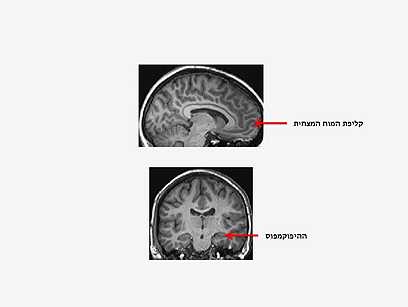

קליפת המוח המצחית, המפותחת לאין ערוך בבני אדם בהשוואה לקופים ותפקידיה תכנון, שיפוט ובקרת תגובה, היא האחרונה להתפתח.

כלומר, ככל שאנו מזדקנים, אזורים במוחנו מתכווצים. זיקנה בריאה מלווה בירידה בנפח קליפת המוח המצחית, המתווכת פונקציות קוגניטיביות גבוהות, וההיפוקמפוס, הנדרש לאחסון אינפורמציה בזיכרון.